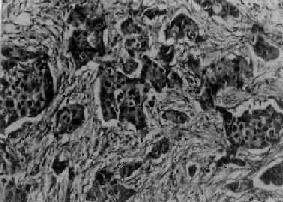

二、乳腺癌乳腺癌很常见,我国乳腺癌的发病率仅次于子宫颈癌而居女性癌瘤的第二位,近年来有不断增加的趋势。常发生于50岁左右的妇女,20岁以前很少见。患者女性亲属中乳腺癌的发病率高于常人2~3倍。其发生原因尚未完全阐明,一般认为可能与雌激素长期作用有关。本癌半数以上发生于乳腺外上象限,其次为乳腺中央区和区上象限。 【类型】 乳腺癌形态结构十分复杂,类型很多。一般根据组织发生和形态结构而将其分为导管癌、小叶癌和特异性癌三大类型:①导管癌,较多见,来源于乳腺导管系统,特别是末梢导管,包括非浸润性导管内癌及浸润性导管癌;②小叶癌,较少见,又称腺泡内癌,来源尚未完全确定,有人认为系起源于肌上皮细胞,也有人认为发生于小叶内导管,包括非浸润性的小叶原位癌及浸润性小叶癌;③特殊型癌,少见,为具有特殊形态结构的一类乳腺癌,如粘液癌、大汗腺样癌、腺样囊性癌、鳞状细胞癌及炎性癌等。 (一)导管内癌 多发生于乳头下乳晕周围,近半数病人在局部可扪及大小不等的肿块或境界不清的肥厚组织。肿块与皮肤无粘连。部分病人表现乳头溢液。由于癌在导管内生长并充满导管腔,致使导管扩张,因而在切面上可见导管为条索状(纵切)或小结节状(横切),灰白色或黄灰色,挤压之可从导管中挤出蠕虫样的半固体性物质。镜检,癌细胞位于扩张的导管内,基底膜完好。癌细胞大小形状不一,细胞分化程度各例不等,分化较高者,核分裂像少见;分化较低的病例,细胞异型性明显,核分裂像多见。其组织结构多样,癌细胞可在扩张的导管内排列成实心团块、乳头状、筛状、小管状,部分病例在管内实体细胞团中央可发生大片坏死,称粉刺性管内癌。 (二)浸润性导管癌 由导管内癌发展而来,为乳腺癌中最常见的类型,约占乳腺癌的50%~80%,以40~60岁妇女为最多见。 【病变】 肉眼观,肿块一般较小,直径多为2~3cm,质硬,边缘不整,常可见到灰白色癌组织呈放射状侵入邻接纤维脂肪组织内。如果癌瘤位置浅,则可侵犯皮肤,与皮肤粘连并导致皮肤出现不规则浅表微小凹陷,呈橘皮样外观;如累及乳头,可出现乳头回缩、下陷现象(图13-25)。镜检,组织形态多样,癌细胞组成实体团块或腺样结构,两者常混合存在。其中多数病例主要由实体癌细胞团组成,称为实体癌。一般根据实体癌的癌实质与纤维组织间质比例的不同,又将其分为单纯癌(simple carcinoma),实质与间质量大致相等(图13-26);硬癌(scirrhous carcinoma),癌实质少而间质多;和不典型髓样癌(atypical medullary carcinoma),癌实质多而间质少,间质内常无淋巴细胞浸润(图13-27),癌细胞常呈多形性,核异型性明显,核分裂像易见。

图13-27 乳腺髓样癌 癌细胞排列成片团状,间质少 (三)小叶原位癌 一般发生于绝经前妇女。临床上一般摸不到肿块,也无症状。标本肉眼观与一般小叶增生不易区别。镜检,癌变小叶体积增大,但小叶轮廓尚保存,小管高度扩张,其中充满单一松散排列的癌细胞。癌细胞呈圆形,大小形状较为一致,核圆形及卵圆形,核分裂像很少。基底膜完整。小叶原位癌经过一定时间可发展为浸润性小叶癌。 (四)浸润性小叶癌 由小叶原位癌突破小管或末梢导管基底膜向间质浸润所致。在大体上很像硬癌,肿块不规则盘状,与周围乳腺组织的边界不清。镜检的特征是癌细胞排列松散,呈条索状;有时为分散的单个癌细胞浸润于成束的纤维组织之间,这些细胞并无组成小叶的痕迹。癌细胞小或中等大小,多呈圆形、椭圆形或梭形,细胞的大小及染色较一致。有时可见从小叶原位癌向浸润性小叶癌过渡的形态。 (五)典型髓样癌 较少见。肿块体积常较大,直径4~6cm或更大,边界较清楚,质松软,灰白色,常杂以灰黄色或暗红色坏死出血区。镜下,癌实质多,间质少。癌细胞较大,圆形、卵圆形,胞浆嗜碱性,核大,染色质丰富,核仁不明显,分裂像较多。间质纤维组织稀少,其中常有淋巴细胞浸润。 本癌一般生长较慢,腋窝淋巴结的转移较少也较晚。预后比浸润性乳腺癌为佳,根治术后5年存活率近70%。